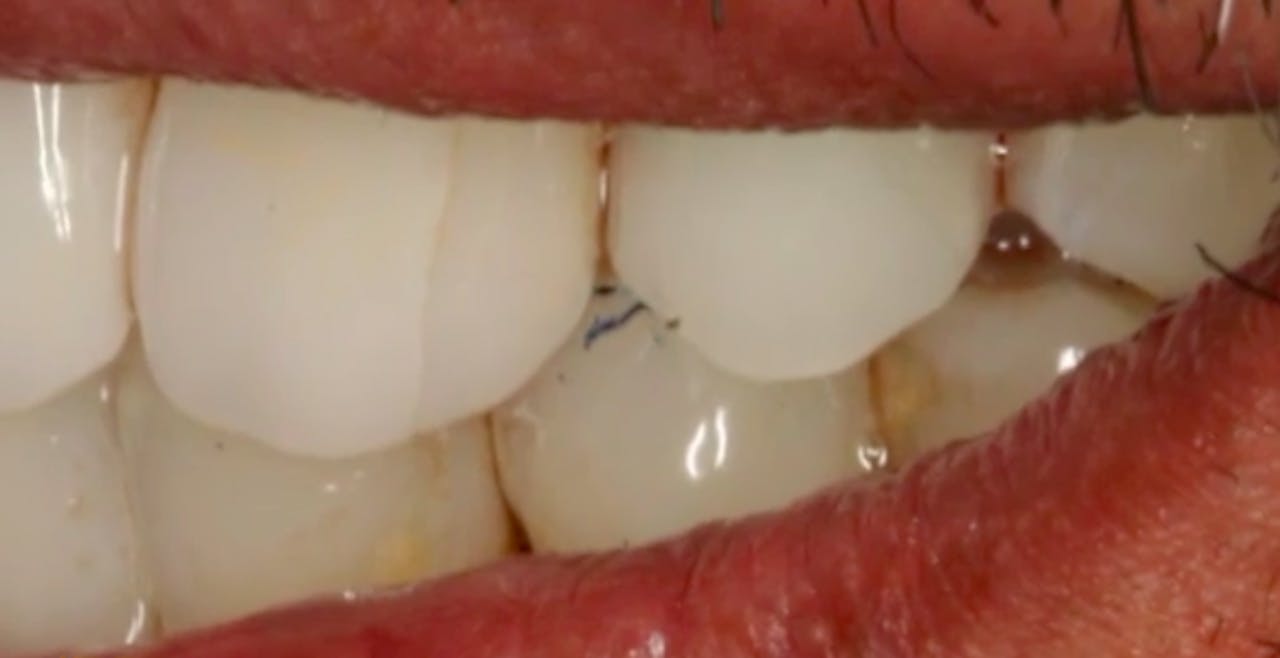

Before / After GIDE Dental Implant Center Gide Dental Reviews Gide dental institute, los angeles, california. 31,762 likes · 74 talking about this · 887 were. Find reviews, ratings, directions, business hours, and book appointments online. Dive deep (at your own pace) in a comprehensive online master class or residency with topics covering implant dentistry, esthetic dentistry,. • 550+ clinical videos on web and app • new dental videos added.. Gide Dental Reviews.

Before / After GIDE Dental Implant Center Gide Dental Reviews Premiere provider of online dental education. Learn from the world's most trusted faculty and advance your skills with gide. Find reviews, ratings, directions, business hours, and book appointments online. Clinical videos, expert interviews, live broadcasts over. Gide dental | 280 followers on linkedin. • 550+ clinical videos on web and app • new dental videos added. Dive deep (at your. Gide Dental Reviews.